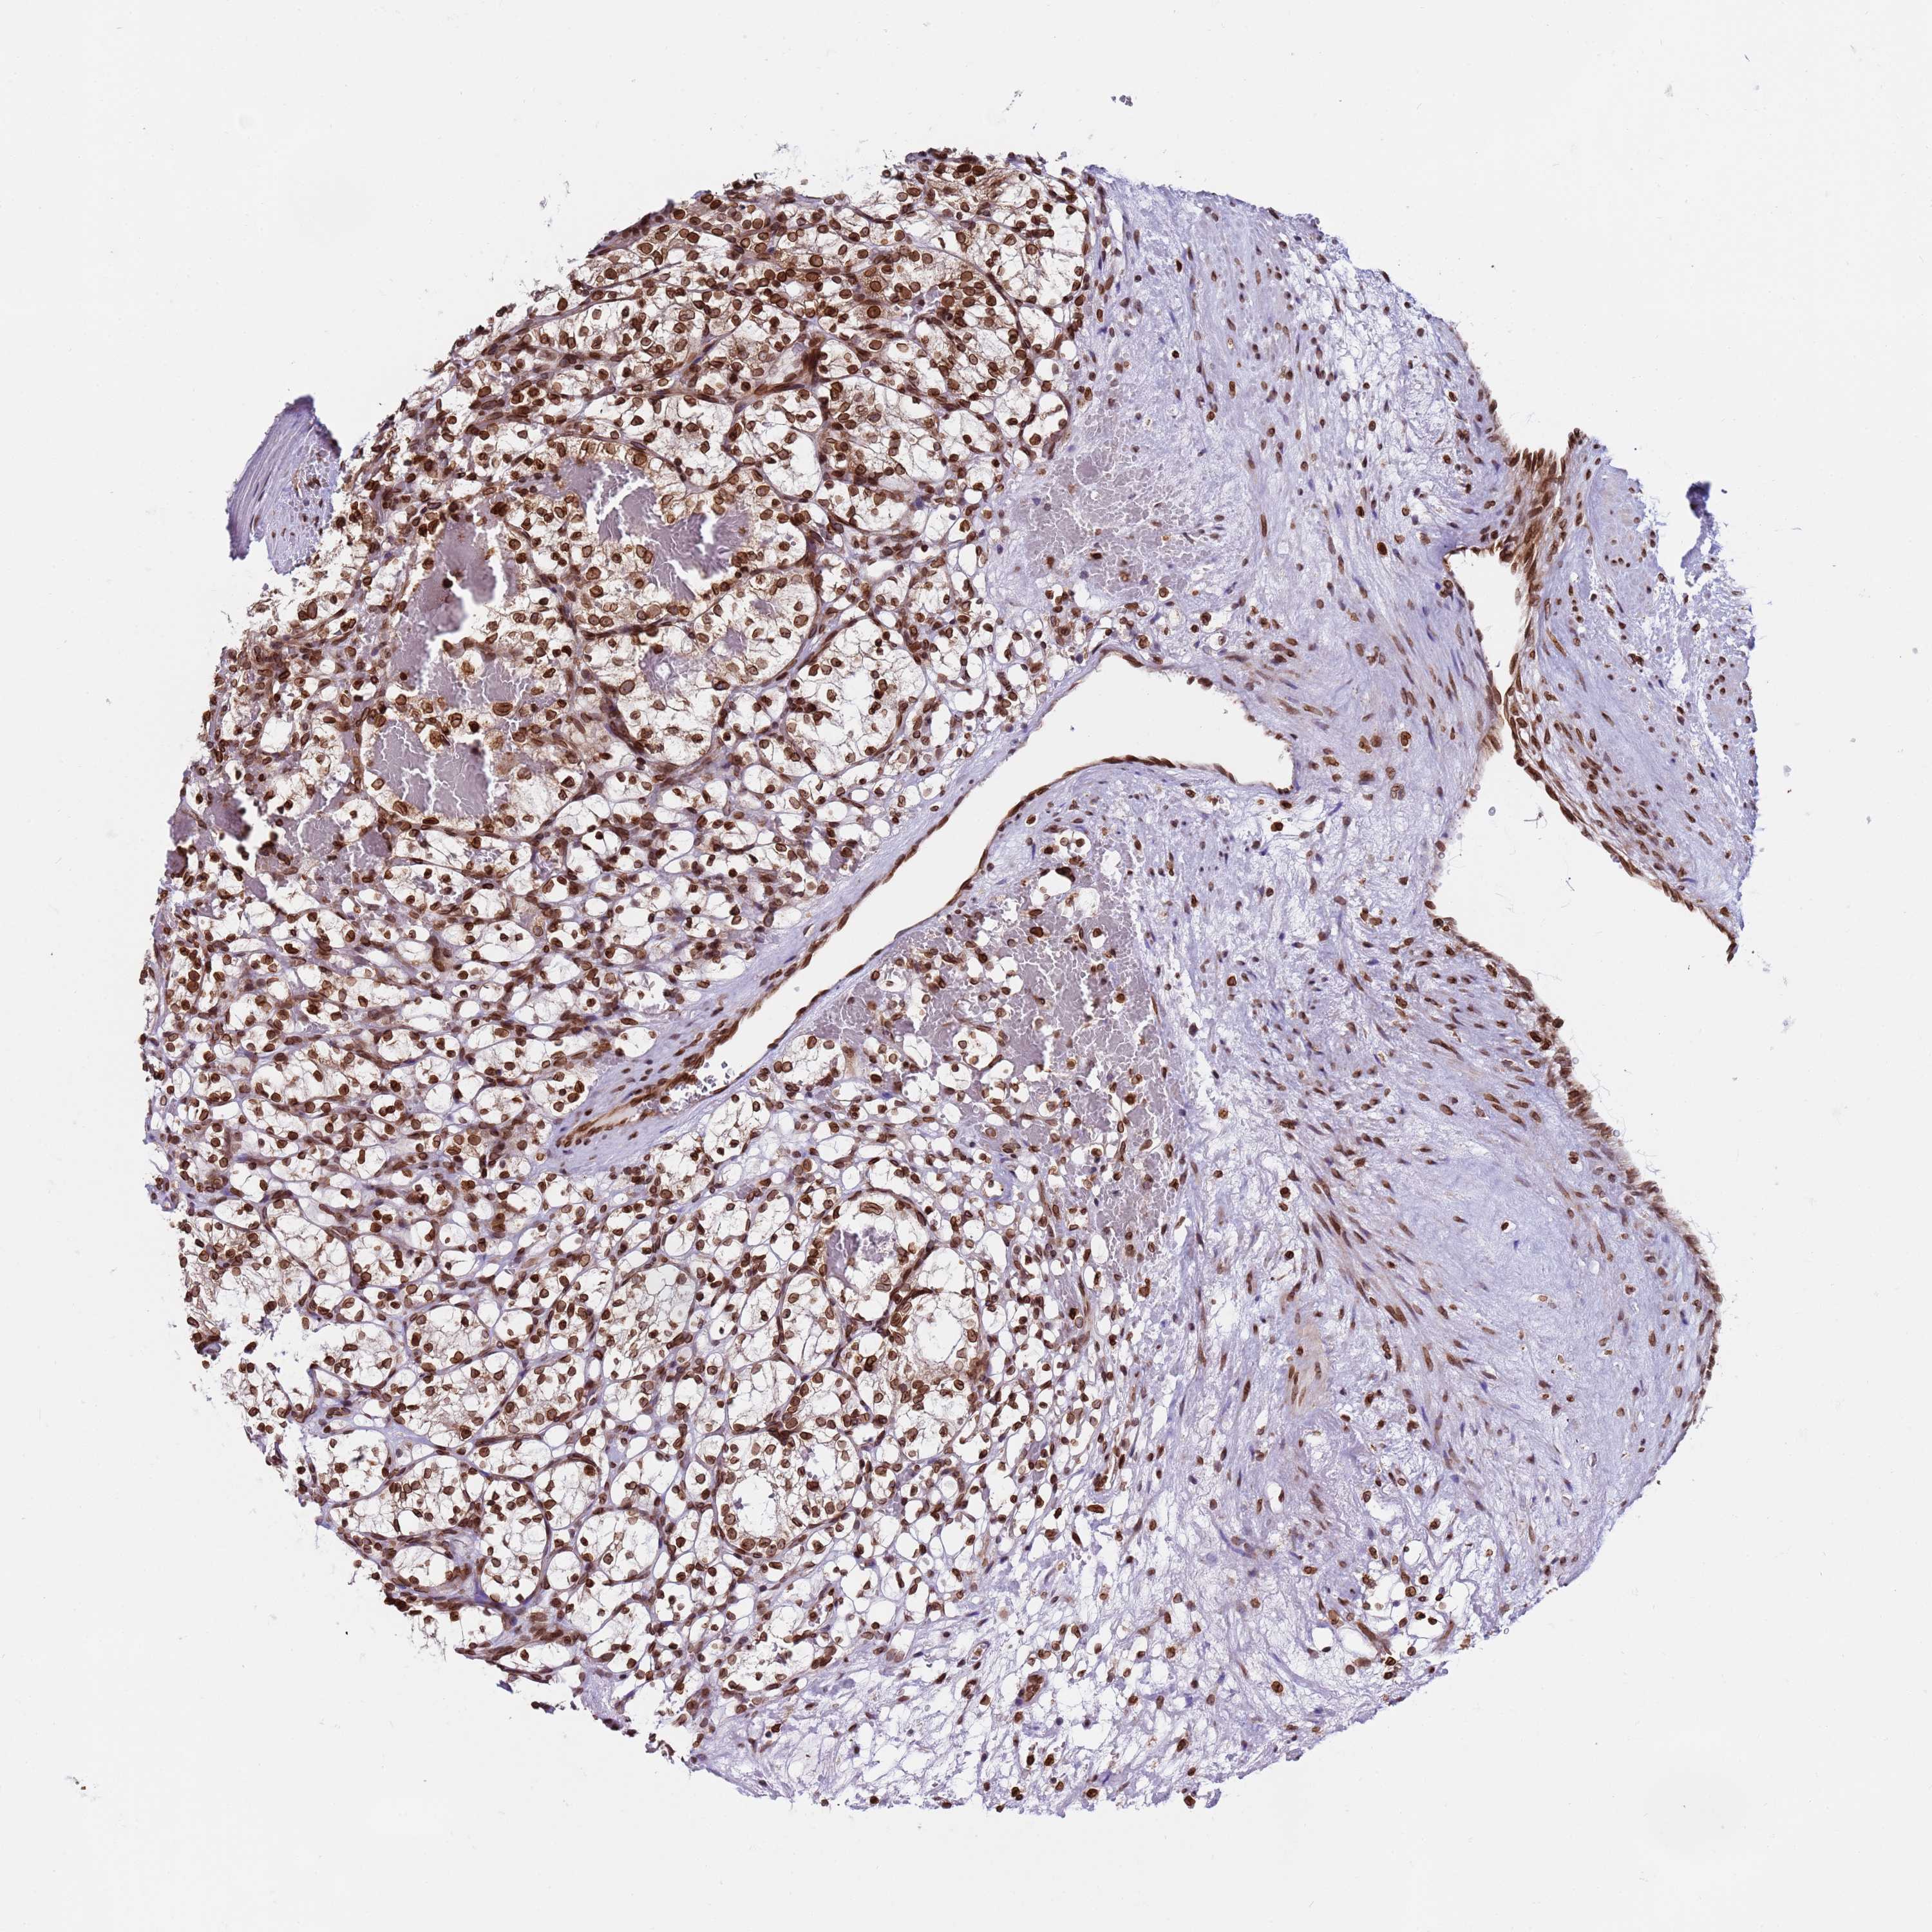

CANCER RENAL CANCER Show tissue menu

KICH TCGA KIRC TCGA KIRC VALIDATION KIRP TCGA PROTEIN RCC CPTAC PROTEIN EXPRESSION

TOR1AIP1 is potential prognostic, high expression is favorable in Kidney Renal Clear Cell Carcinoma (TCGA)